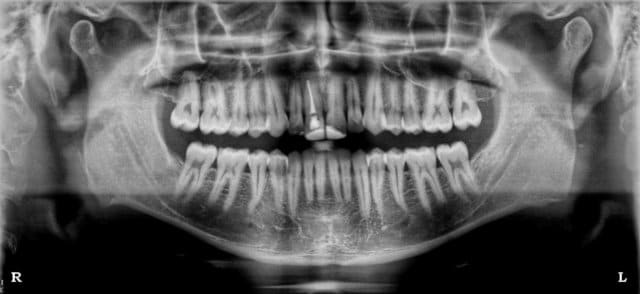

Cet appareil est visible et essayable dans l'est et dans l'ouest de Paris.

Clichés dispos en pièce jointe.

dis JAOUI , il est drolement bien le bloc antérieur sur ta panoramique sans filtre , mais dis-moi , tu l'a prise avec ou sans flach ...